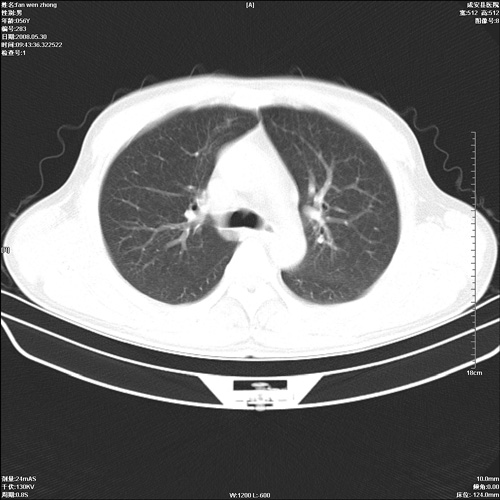

病人 男 56岁 一周前高热,体温达39-40度,经抗炎治疗后,体温渐降,达37,5-38度,轻微咳嗽,胸部不适 查白细胞为1.3万 行ct检查,请分析。

双肺内可见多发结节状病灶,并见小空洞,病人高热,白血球增高,应该是典型的迁徙性肺脓肿(多为金黄色葡萄球菌感染)。查一下口腔等其它部位有无感染灶。

双肺内可见多发结节状病灶,并见小空洞,病人高热,白血球增高,应该是典型的迁徙性肺脓肿(多为金黄色葡萄球菌感染)。建议治疗后复查.